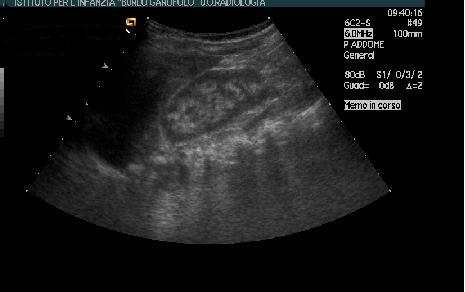

Ecografia rene, con evidenza di un quadro di nefrocalcinosi (Figura 2). La creatinina sierica e la pressione arteriosa sono comunque nella norma.

Figura 2. Ecografia renale

Iperecogenicit� midollare con marcata differenziazione cortico-midollare in un quadro di chiara nefrocalcinosi.